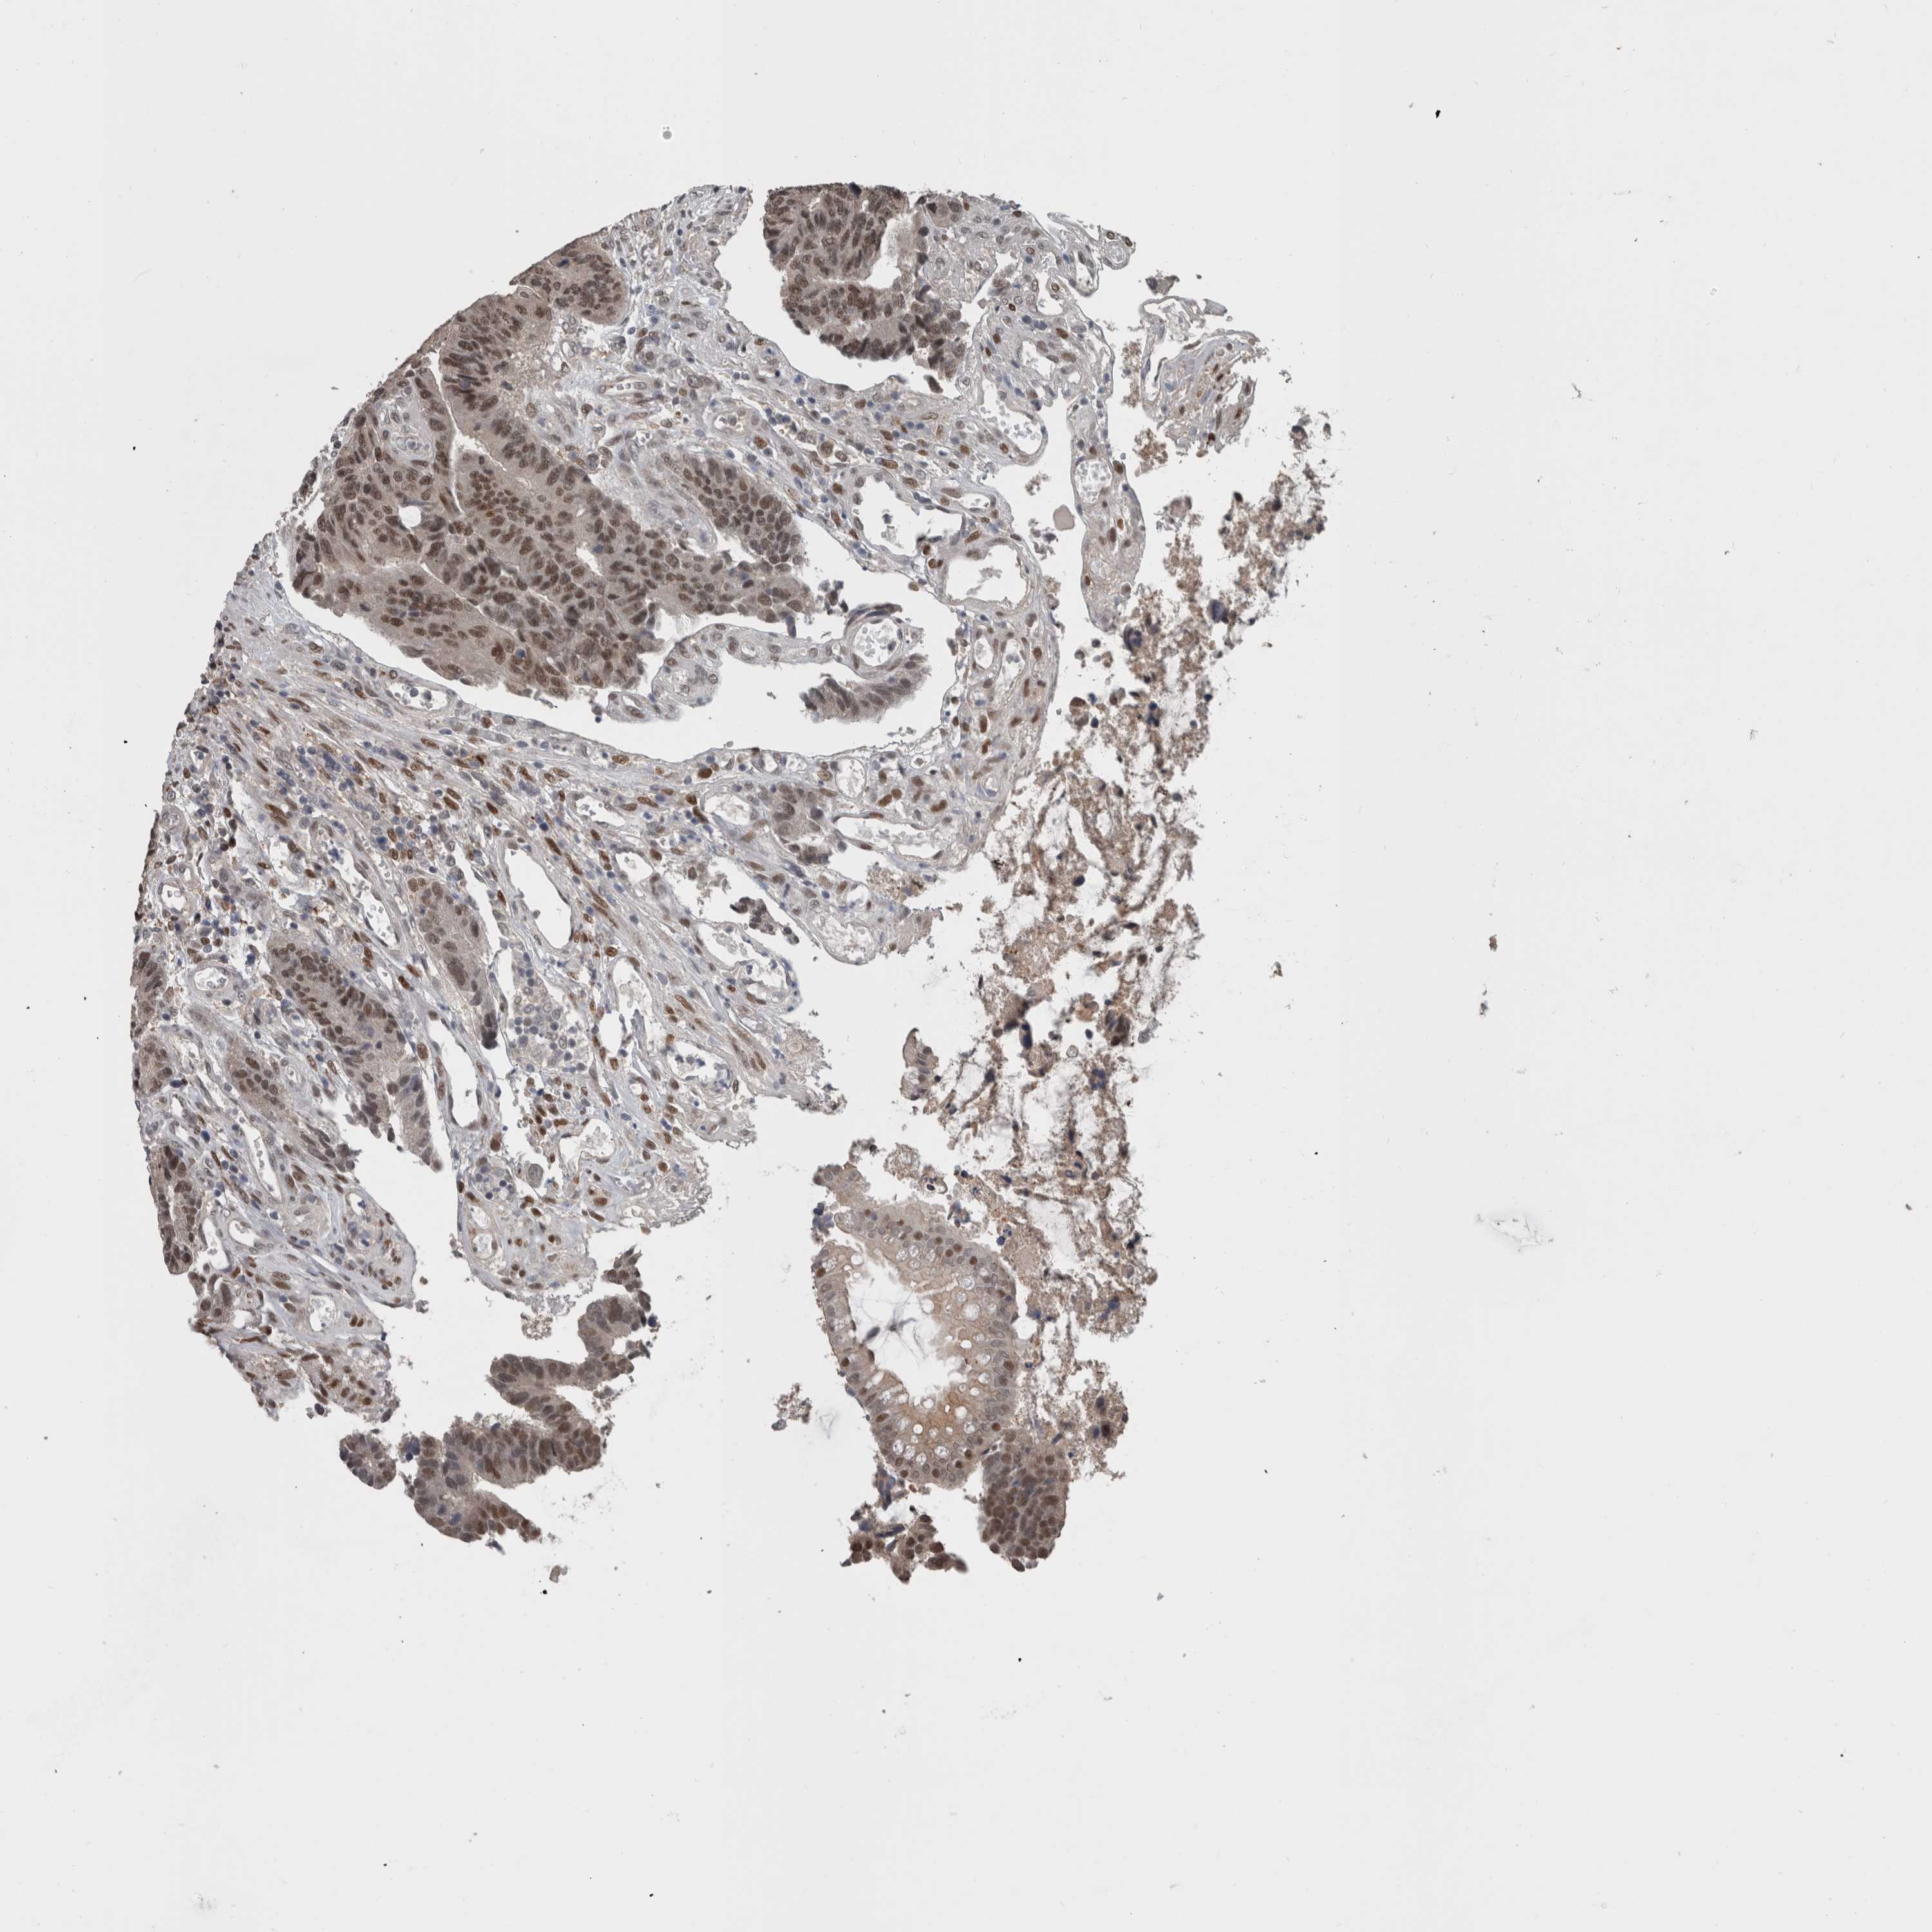

CANCER COLORECTAL CANCER Show tissue menu

Colorectal cancer

Human cancer

Colon adenocarcinoma